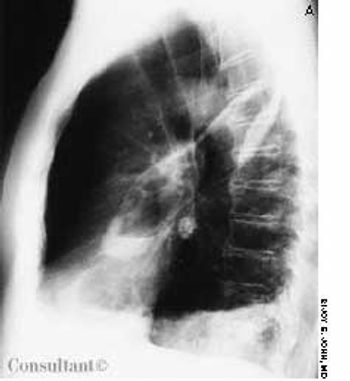

A 58-year-old man with a history of a seizure disorder was hospitalized with acute-onset shortness of breath immediately following a tonic-clonic seizure. He was afebrile; in respiratory distress; and hypoxic, with an oxygen saturation of 84% on room air.

A 58-year-old man with a history of a seizure disorder was hospitalized with acute-onset shortness of breath immediately following a tonic-clonic seizure. He was afebrile; in respiratory distress; and hypoxic, with an oxygen saturation of 84% on room air. Auscultation revealed bibasilar crackles and an S3 gallop. The patient was given noninvasive mechanical ventilatory support, oxygen, and diuretics.